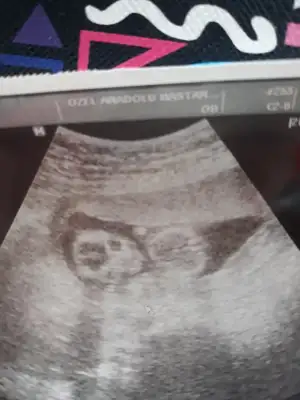

burdan bellimi bisiler, ultrsn kagidindan belli degil demistin,13 haft.bu sonradan aklima geldi bunu atmak 😊😊

Oglum var bitane 5 yasinda.enn onemlisi saglikli olmasi benm bnm icin elbette, merak iste kizdir belki diye kontrolüme de var bi 20 gun falan.

Diger usg de tam hatırlamıyorum sanki kız gibi demiştim